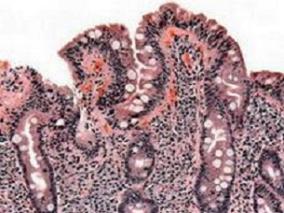

1小时条评论奥美沙坦相关严重口炎性腹泻样肠病已被报道,但尚无流行病学研究证据证明风险增加。2016年10月,发表在《Gut》的一项研究旨在评价一个全国患者队列中,与其他血管紧张素受体阻断剂(ARB)和ACE抑制剂(ACEIs)相比,奥美沙坦相关小肠吸收不良住院的风险。结果表明,...